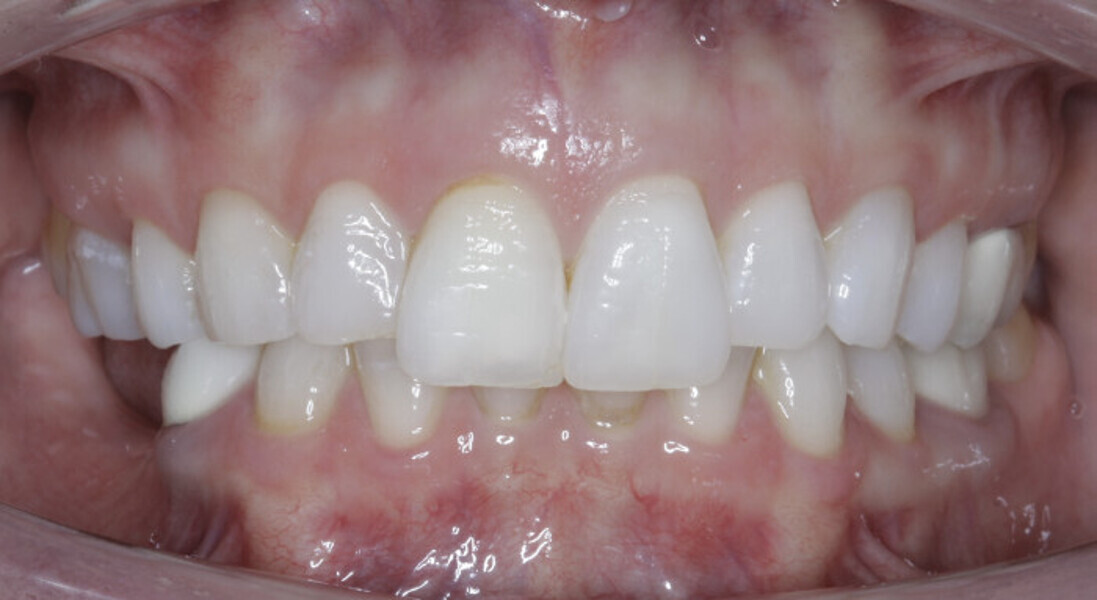

New Age orthodontics and orthopaedics with temporary anchorage devices